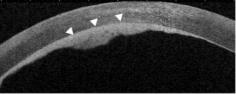

- 前节OCT:左眼角膜溃疡表面平整,后弹力层连续,内皮面见高反射均质内皮斑,与后弹力层界限清楚。

- 真菌性角膜炎出现内皮斑标志着真菌菌丝穿凿破坏后弹力层进入前房,因此前节OCT表现为后弹力层连续性中断,内皮斑形态不规则。

- 病毒性角膜炎出现内皮斑是因为炎性细胞在角膜后面大量聚集,是炎症反应重的标志,因此前节OCT表现为后弹力层连续完整,内皮斑均质且形态规则。